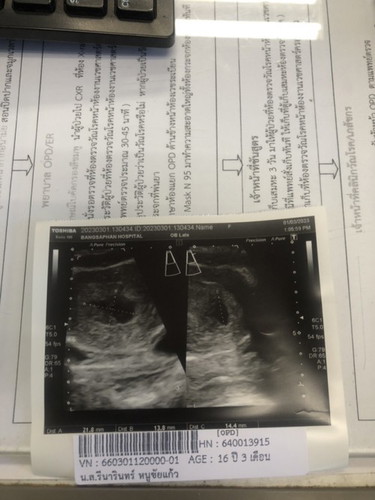

10 วีค อัตราซาวผ่านหน้าท้องไม่เจอตัวอ่อน มีโอกาสท้องลมไหมคะ พรุ่งนี้หมอนัดซาวช่องคลอดค่ะ

อายุครรภ์น้อยต้องซาวทางช่องคลอดถึงจะเห็นชัดค่ะ แต่10wแล้วโอกาศท้องลมสูงมากค่ะ

10wน้องเป็นรูปร่างคนเเล้วงับ รอดู พนนะคะ เสี่ยงท้องลมสูง